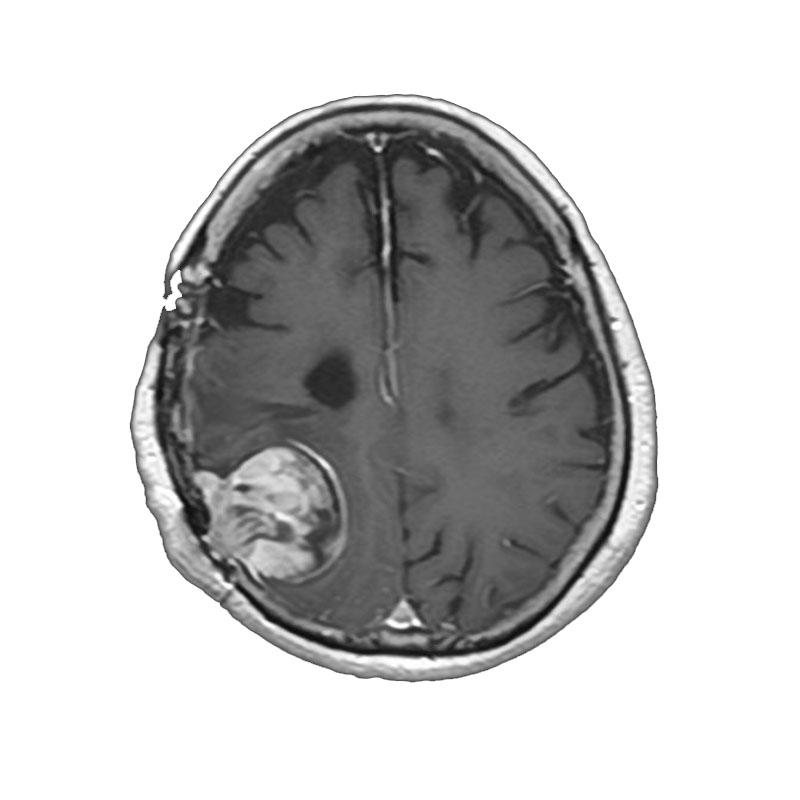

右側頭葉脳腫瘍

摘出術

南田/野本/佐伯